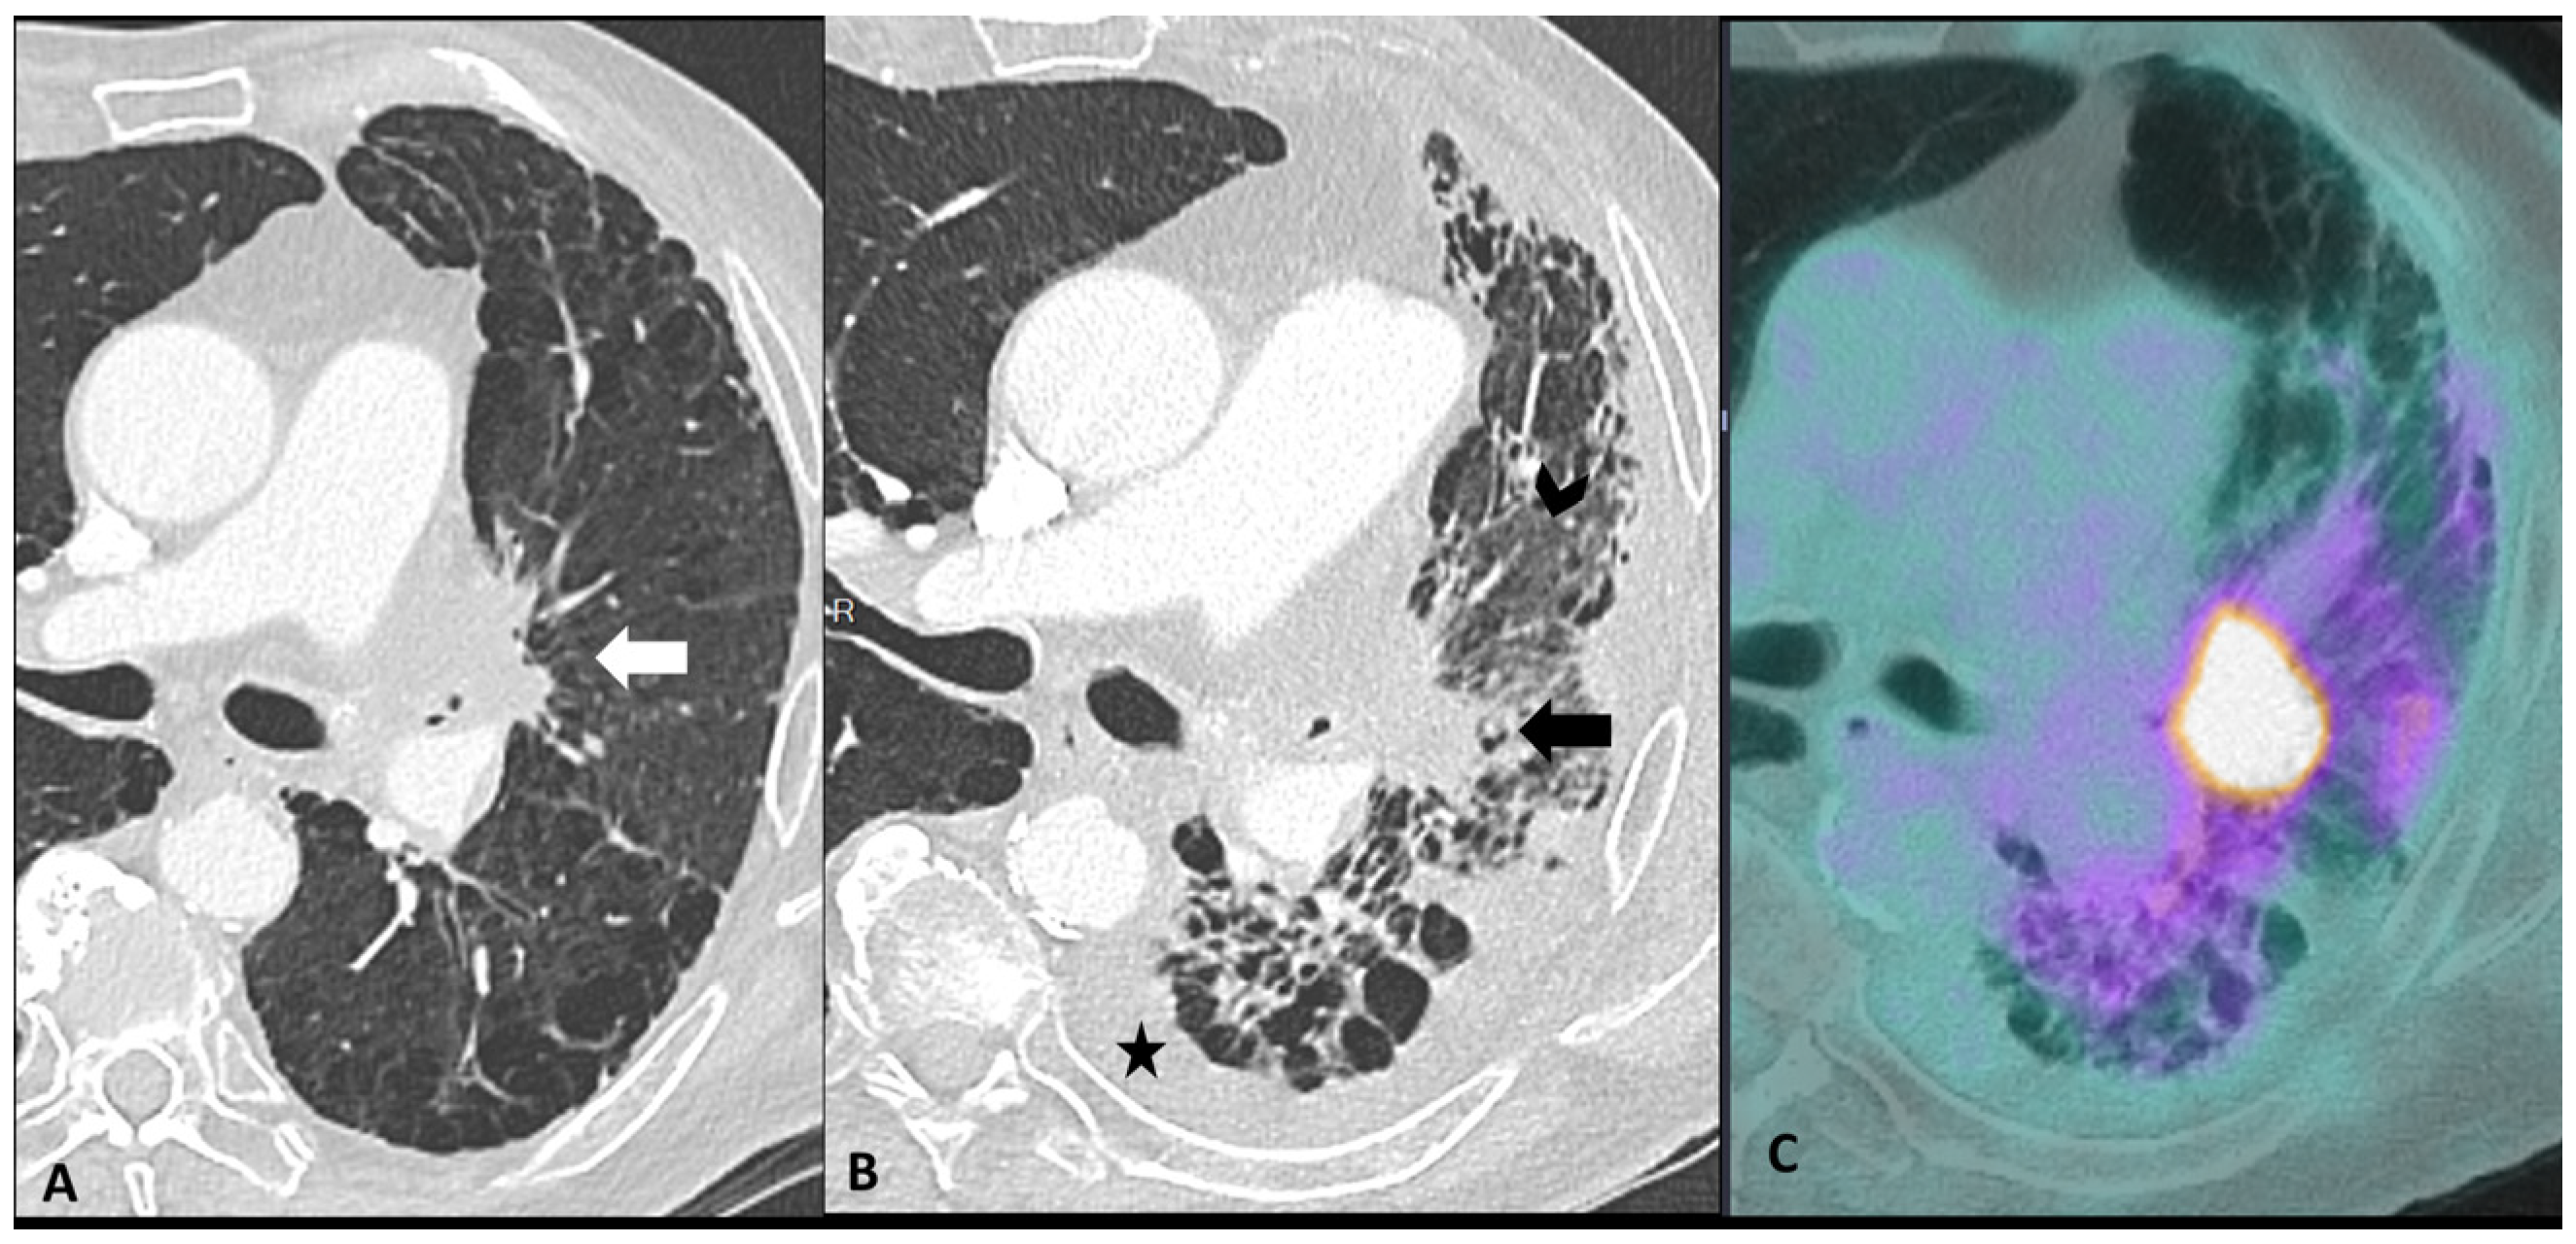

2.2.2. Sarcoidosis-Like Reaction

- Gkiozos, I.; Kopitopoulou, A.; Kalkanis, A.; Vamvakaris, I.N.; Judson, M.A.; Syrigos, K.N. Sarcoidosis-Like Reactions Induced by Checkpoint Inhibitors. J. Thorac. Oncol. 2018, 13, 1076–1082. [Google Scholar] [CrossRef] [PubMed]

| Other toxicities | Sarcoidosis-like Reaction | Enlarged hilar and mediastinal lymph nodes +/− bilateral perylimphatic (mainly scissural) micronodules | Bilateral and symmetrical | Lymph node metastasis disease Lymphangitis |